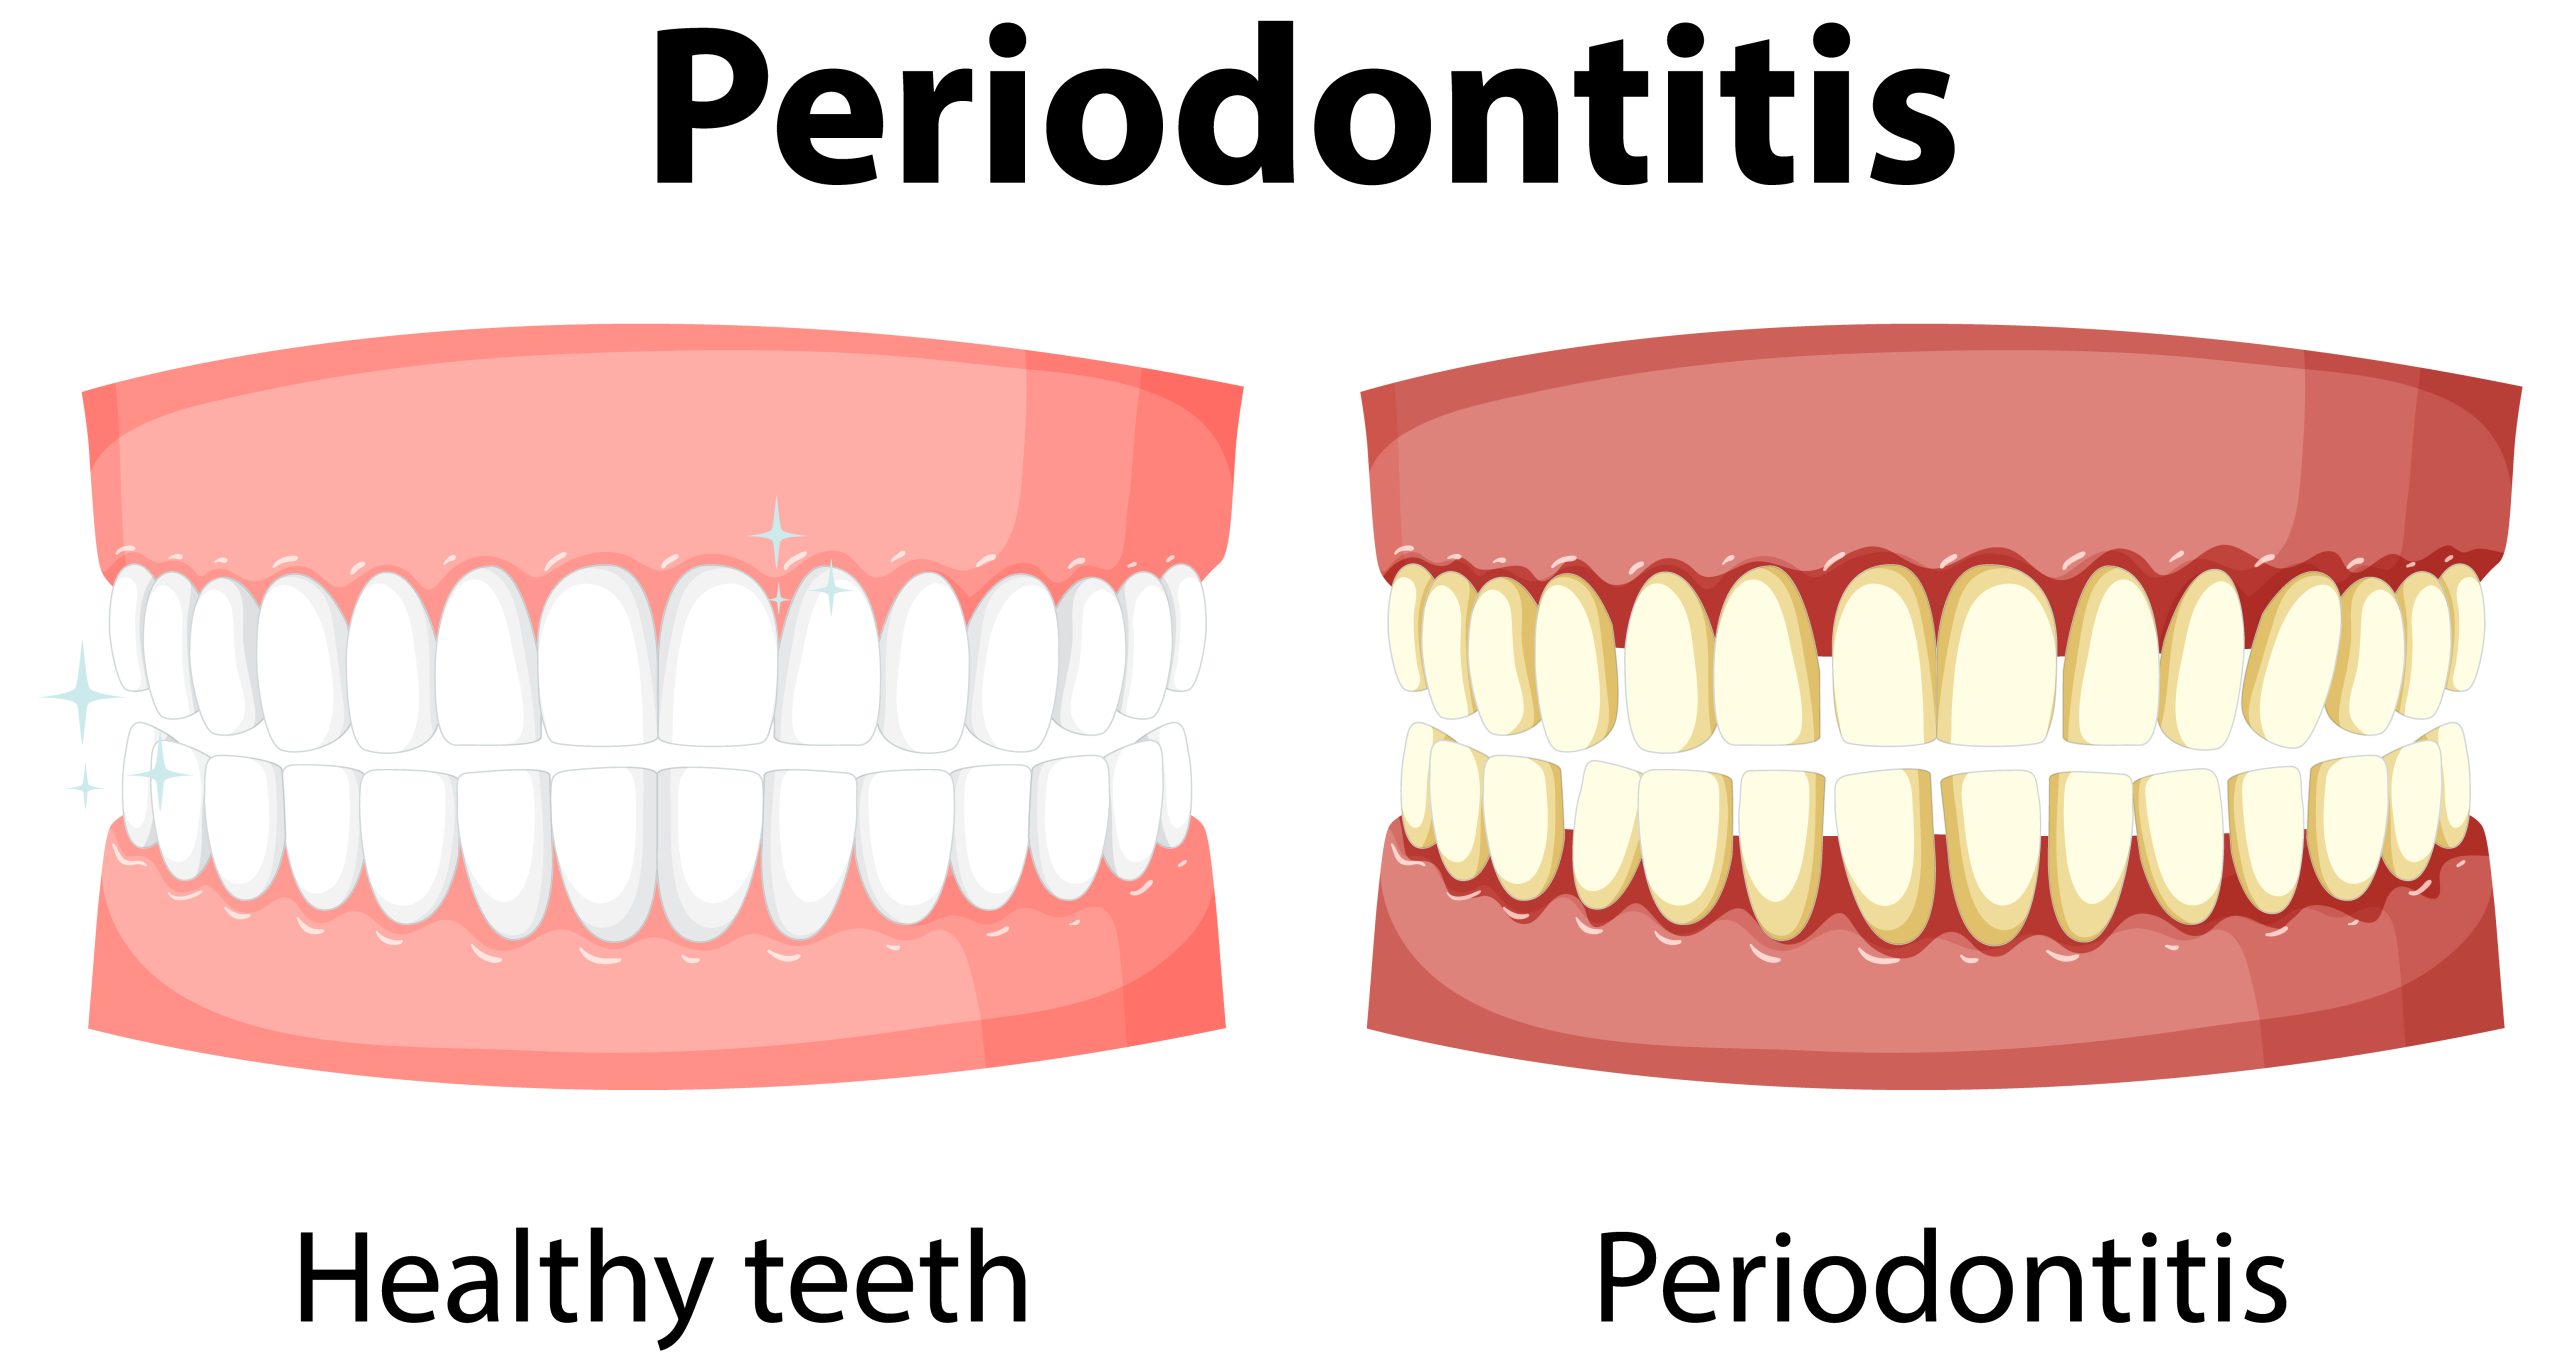

Gum disease, also known as periodontal disease, is an infection and inflammation of the tissues that support your teeth.

There are two main stages: